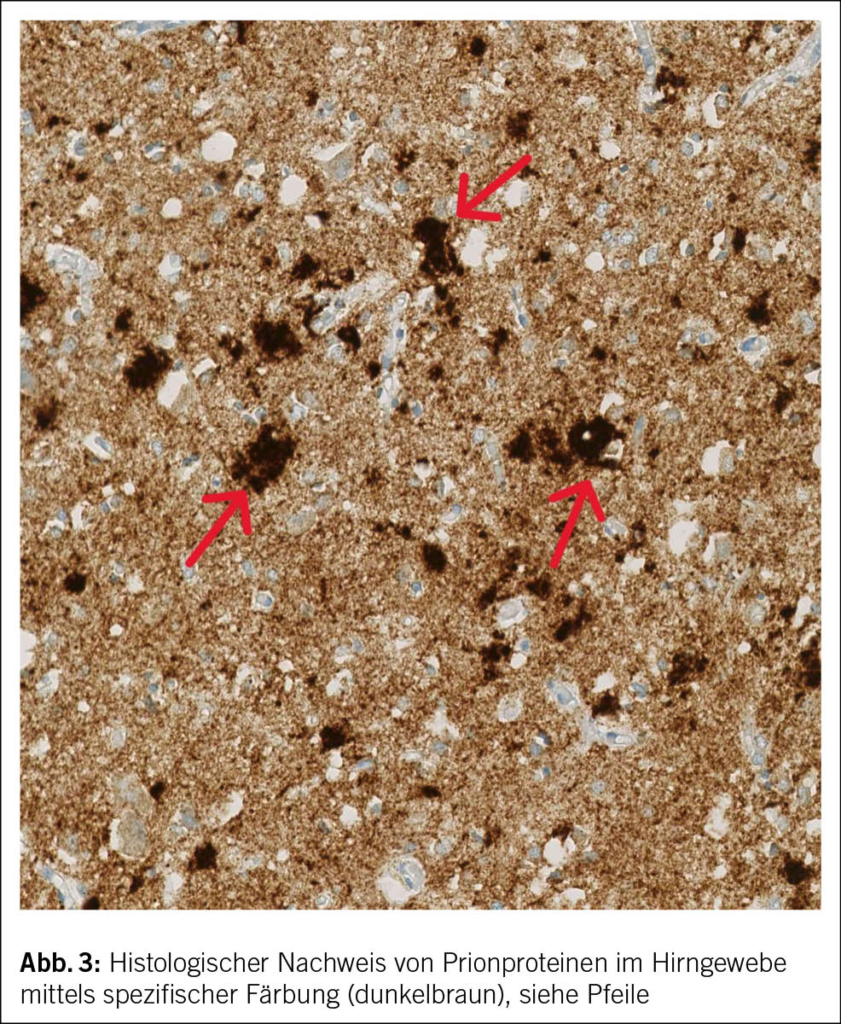

Bei charakteristischer Klinik mit rasch progredientem Verlauf und den typischen Befunden im MRI des Schädels sowie in Liquor und EEG lag bei beiden Patienten das Bild einer sCJD vor. Bei Patient 2 wurde die Diagnose post mortem in der Histopathologie des Hirngewebes gesichert (Abb. 3).

Biopsie

Da eine definitive Diagnose nur histopathologisch gestellt werden kann, ist die Hirnautopsie bzw. -biopsie weiterhin der Goldstandard zur Diagnose einer sCJD (6, 24). Die Hirnbiopsie erfolgt aufgrund der Invasivität und oft auch fehlender Verfügbarkeit der Diagnostik (24) in der Regel erst post mortem. Es besteht das Risiko eines falsch negativen Resultats, da die fehlgefalteten Prionen nicht in allen Hirnregionen zu finden sind (15).